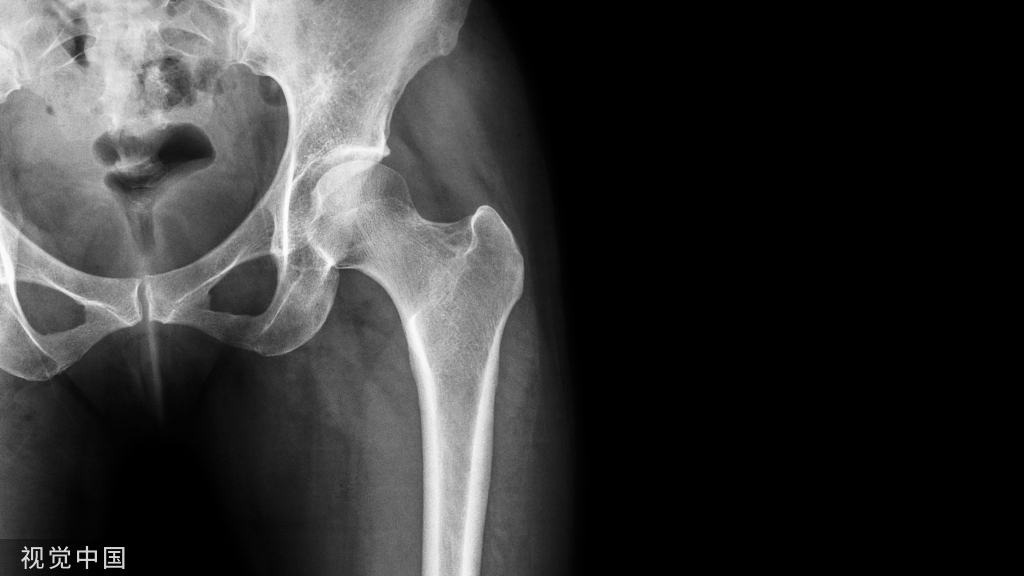

本随机临床对照试验纳入了从 2015 年 1 月 1 日至 2017 年 6 月 30 日期间接受手术治疗的胫骨平台或 Pilon 骨折符合高感染风险标准的成年患者,共 12 个月36 个美国创伤中心的随访(最终随访评估于 2018 年 4 月完成)。